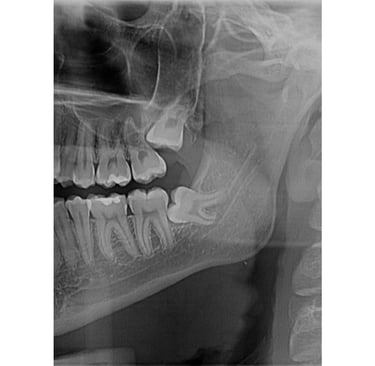

Impaktirani umnjaci su treći stalni molari koji često ne mogu da izniknu te ih je neophodno odstraniti.

Impaktirani umnjaci su treći stalni molari koji često ne mogu da izniknu te ih je neophodno odstraniti.Hirurška ekstrakcija je rutinska oralnohirurška intervencija koja se izvodi u lokalnoj anesteziji. Naš tim se trudi da ova intervencija prođe što bezbolnije i sa manjim otokom.Pre i posle intervencije ćete dobiti sve neophodne savete. Za jako plašljive, postoji mogućnost sedacije azot-suboksidom radi oslobađanja straha.